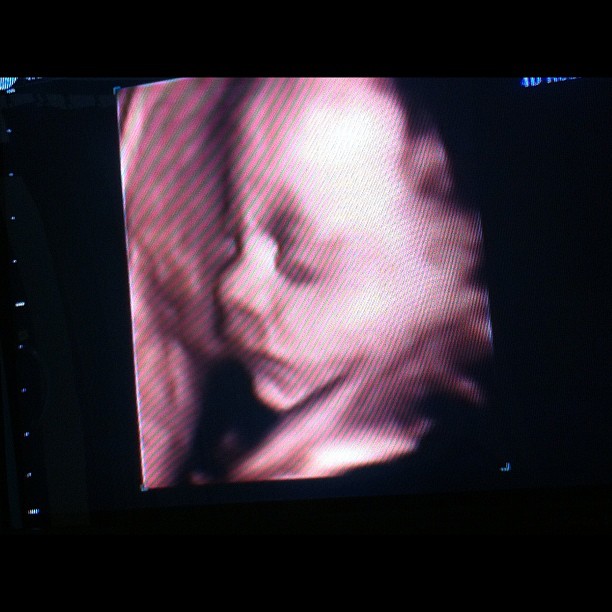

ส่วนลูกชายของหนุ่มและฝ้าย จะดูหล่อขนาดไหน คงไม่ต้องบรรยายอะไรมาก เพราะหนุ่ม ทำรูปเปรียบเทียบด้านข้างระหว่างคุณพ่อกับคุณลูกมาให้เห็นกันจะ ๆ ชนิดที่ต้องบอกว่า คุณลูกได้ดีเอ็นเอคุณพ่อมาเต็ม ๆ คัดลอกสำเนาถูกต้องกันมาแบบเป๊ะ ๆ ทุกกระเบียดนิ้ว